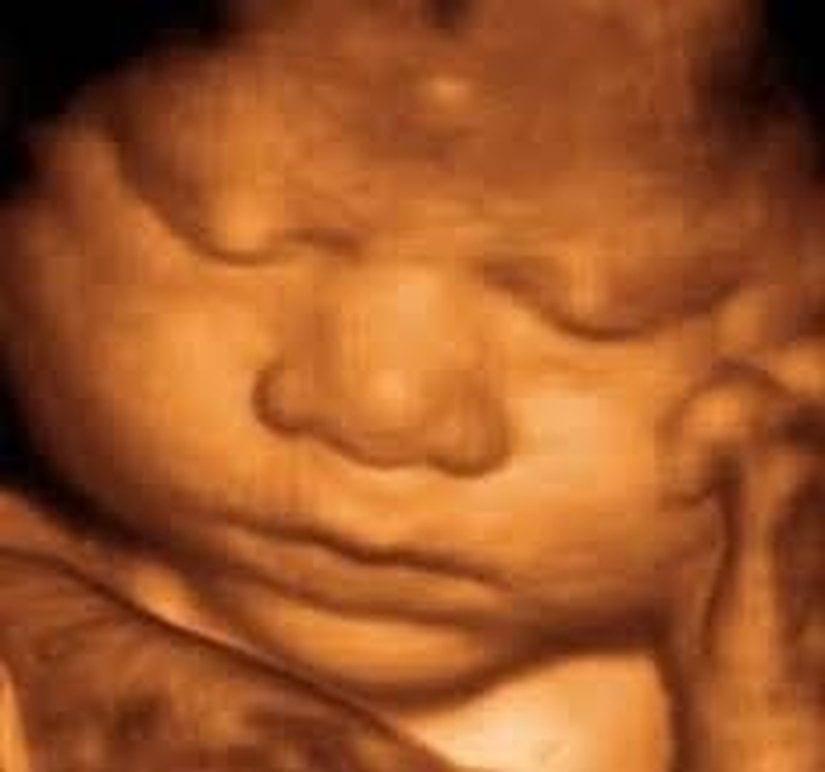

Ama giderek popülerleşen bir teknoloji sayesinde ebeveynler artık yavrularını çok daha net görebiliyorlar: 3D ve hatta 4D ultrason! Monako'daki Princes Grace Hastanesi'nde görev yapan Dr. Bernard Benoit, uzun yıllardır 3 boyutlu (ve hatta 4 boyutlu) ultrason görüntüleme teknikleri üzerinde çalışıyor ve çok başarılı sonuçlara da imza atmış vaziyette. Aşağıda, bunun bir örneğini görüyorsunuz.

Bu görüntüleme tekniği sayesinde, artık renkli ve çok daha net sonuçlara ulaşabiliyoruz. Bu görseller, bunun en net ispatlarından biri. Ana karnındaki ikizleri çok detaylı bir şekilde görüntülemek artık mümkün. Hem de o, uzaktan odaklanılmış bir kare. Aşağıdakiler, ne demek istediğimizi daha net anlatacaktır:

3D ultrasonlarda, birden fazla açıdan 2 boyutlu görüntüler çekiliyor ve sonrasında bilgisayar yardımıyla 3 boyutlu bir görsele dönüştürülüyor. Bu sayede bebeğinizin sadece bir kesidini değil, 3 boyutlu bir görüntüsünü elde etmeniz mümkün oluyor.